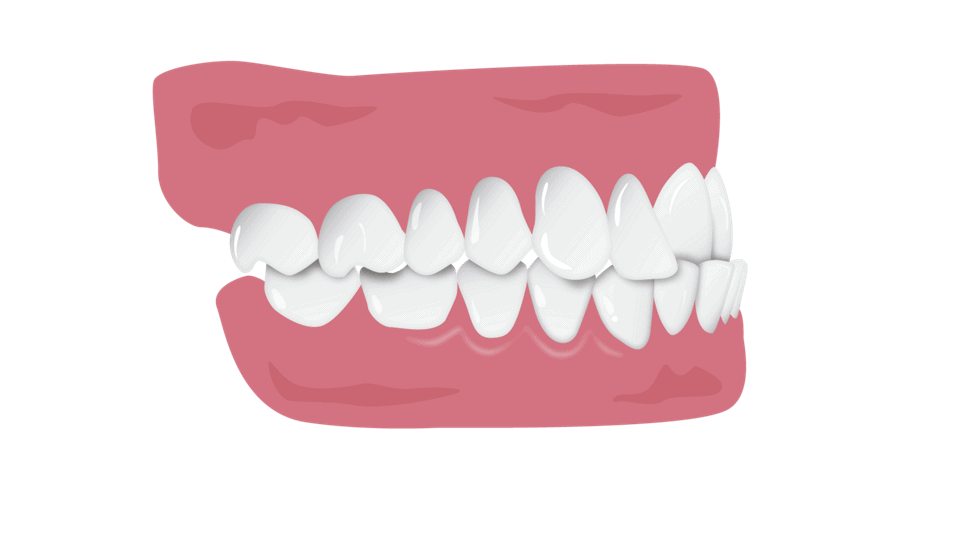

Štrleči zobje

Vaši zgornji zobje štrlijo preveč čez spodnje sprednje zobe.

Zakaj jih popraviti?

Prekomerno štrleči zobje otežijo grizenje in žvečenje hrane in lahko povzroči resne težave z zdravjem ust, kot so zlomi zob in izguba kosti.

Ali lahko nevidni aparati pomagajo?

Prej / Potem *